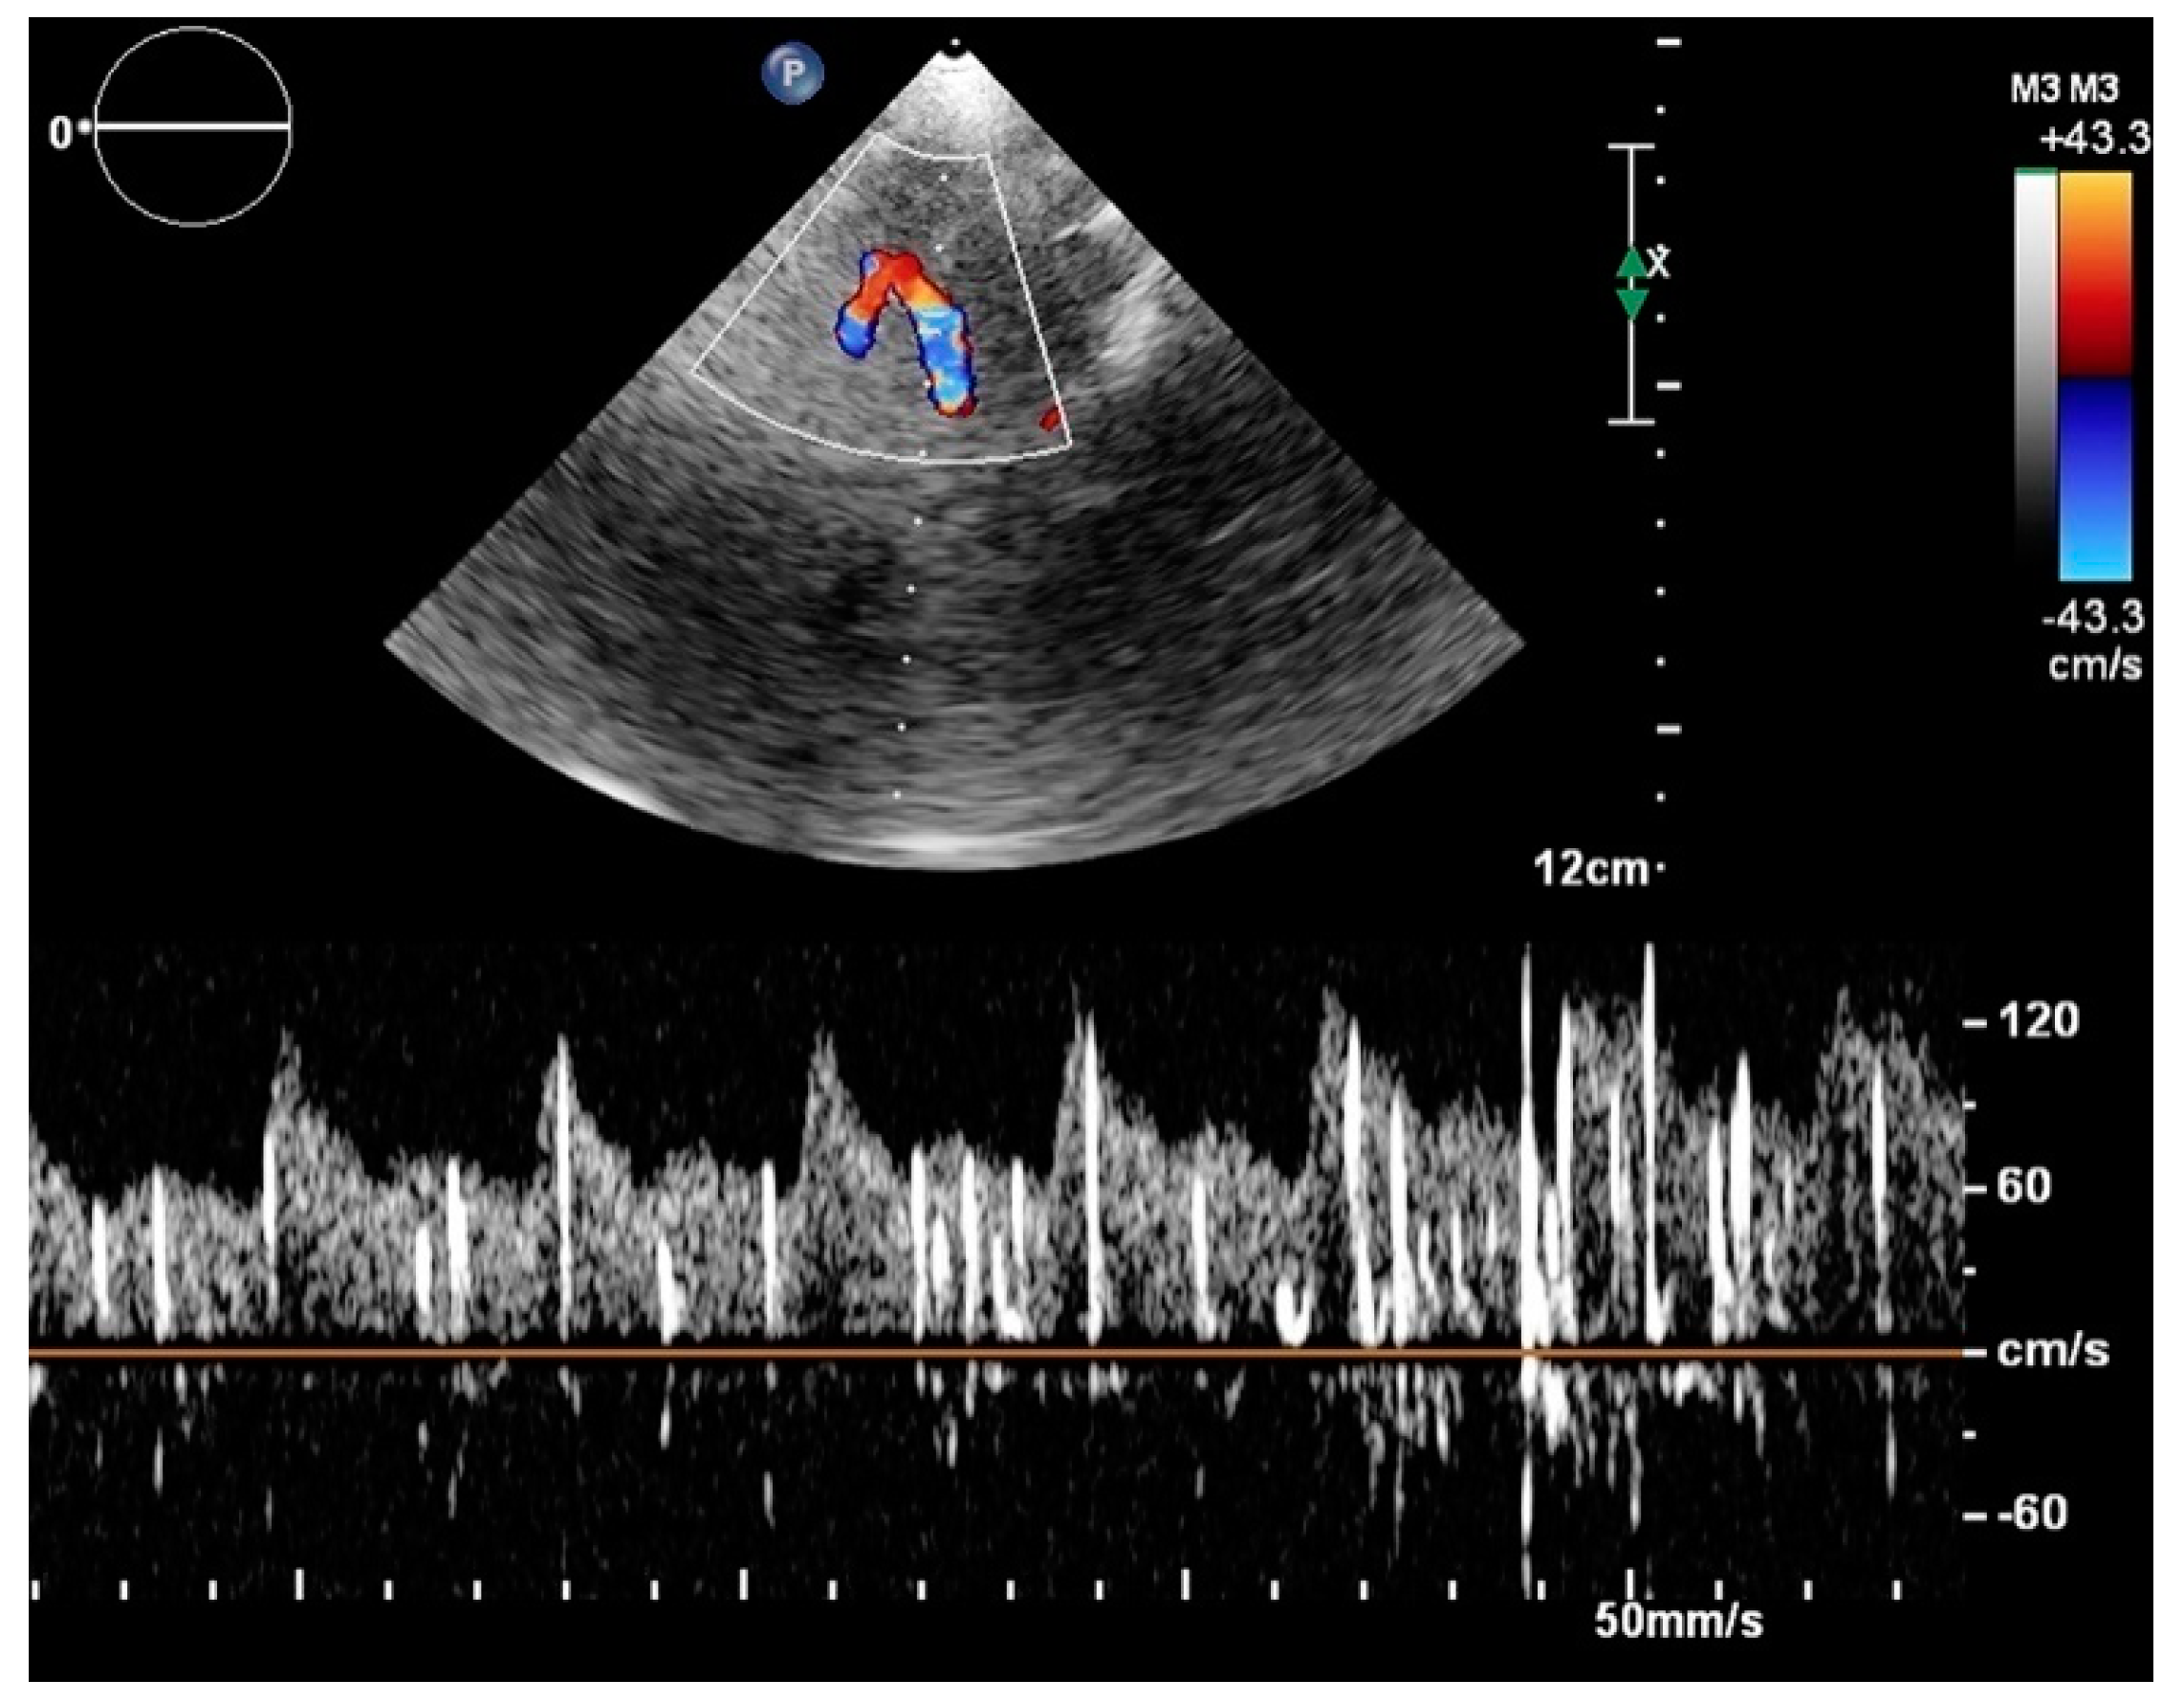

- Vitarelli, A. Patent foramen ovale: Pivotal role of transesophageal echocardiography in the indications for closure, assessment of varying anatomies and post-procedure follow-up. Ultrasound Med. Biol. 2019, 45, 1882–1895. [Google Scholar] [CrossRef]

- Zivanovic, Z.; Ruzicka-Kaloci, S.; Jesic, A.; Radovanovic, B.; Lucic-Prokin, A.; Slankamenac, P. Paradoxical emboli: Clinical importance of transcranialdoppler for detection of patent foramen ovale. Med. Pregl. 2010, 63, 445–449. [Google Scholar] [CrossRef]

- Nedeltchev, K.; Mattle, H.P. Contrast-enhanced transcranial doppler ultrasound for diagnosis of patent foramen ovale. Front. Neurol. Neurosci. 2006, 21, 206–215. [Google Scholar]